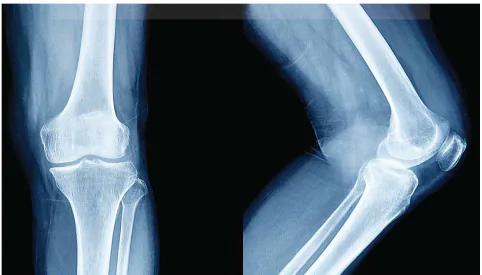

Hình 5.2 là ảnh chụp X-quang, từ ảnh chụp ta thấy xương có màu trắng, các mô mềm có màu đậm hơn, lí do là xương hấp thụ tia X tốt hơn so với các mô mềm.

Hình 5.2. Hình ảnh chụp X- quang